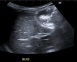

Perforated appendicitis with faecolith in an infant

A seven-month-old, previously well, Caucasian male infant presented in the emergency department with one-day history of runny nose, vomiting, decrease oral intake and low grade fever. He was discharged after a short stay with suspected gastroenteritis.

He presented again with irritability, decreased urine...